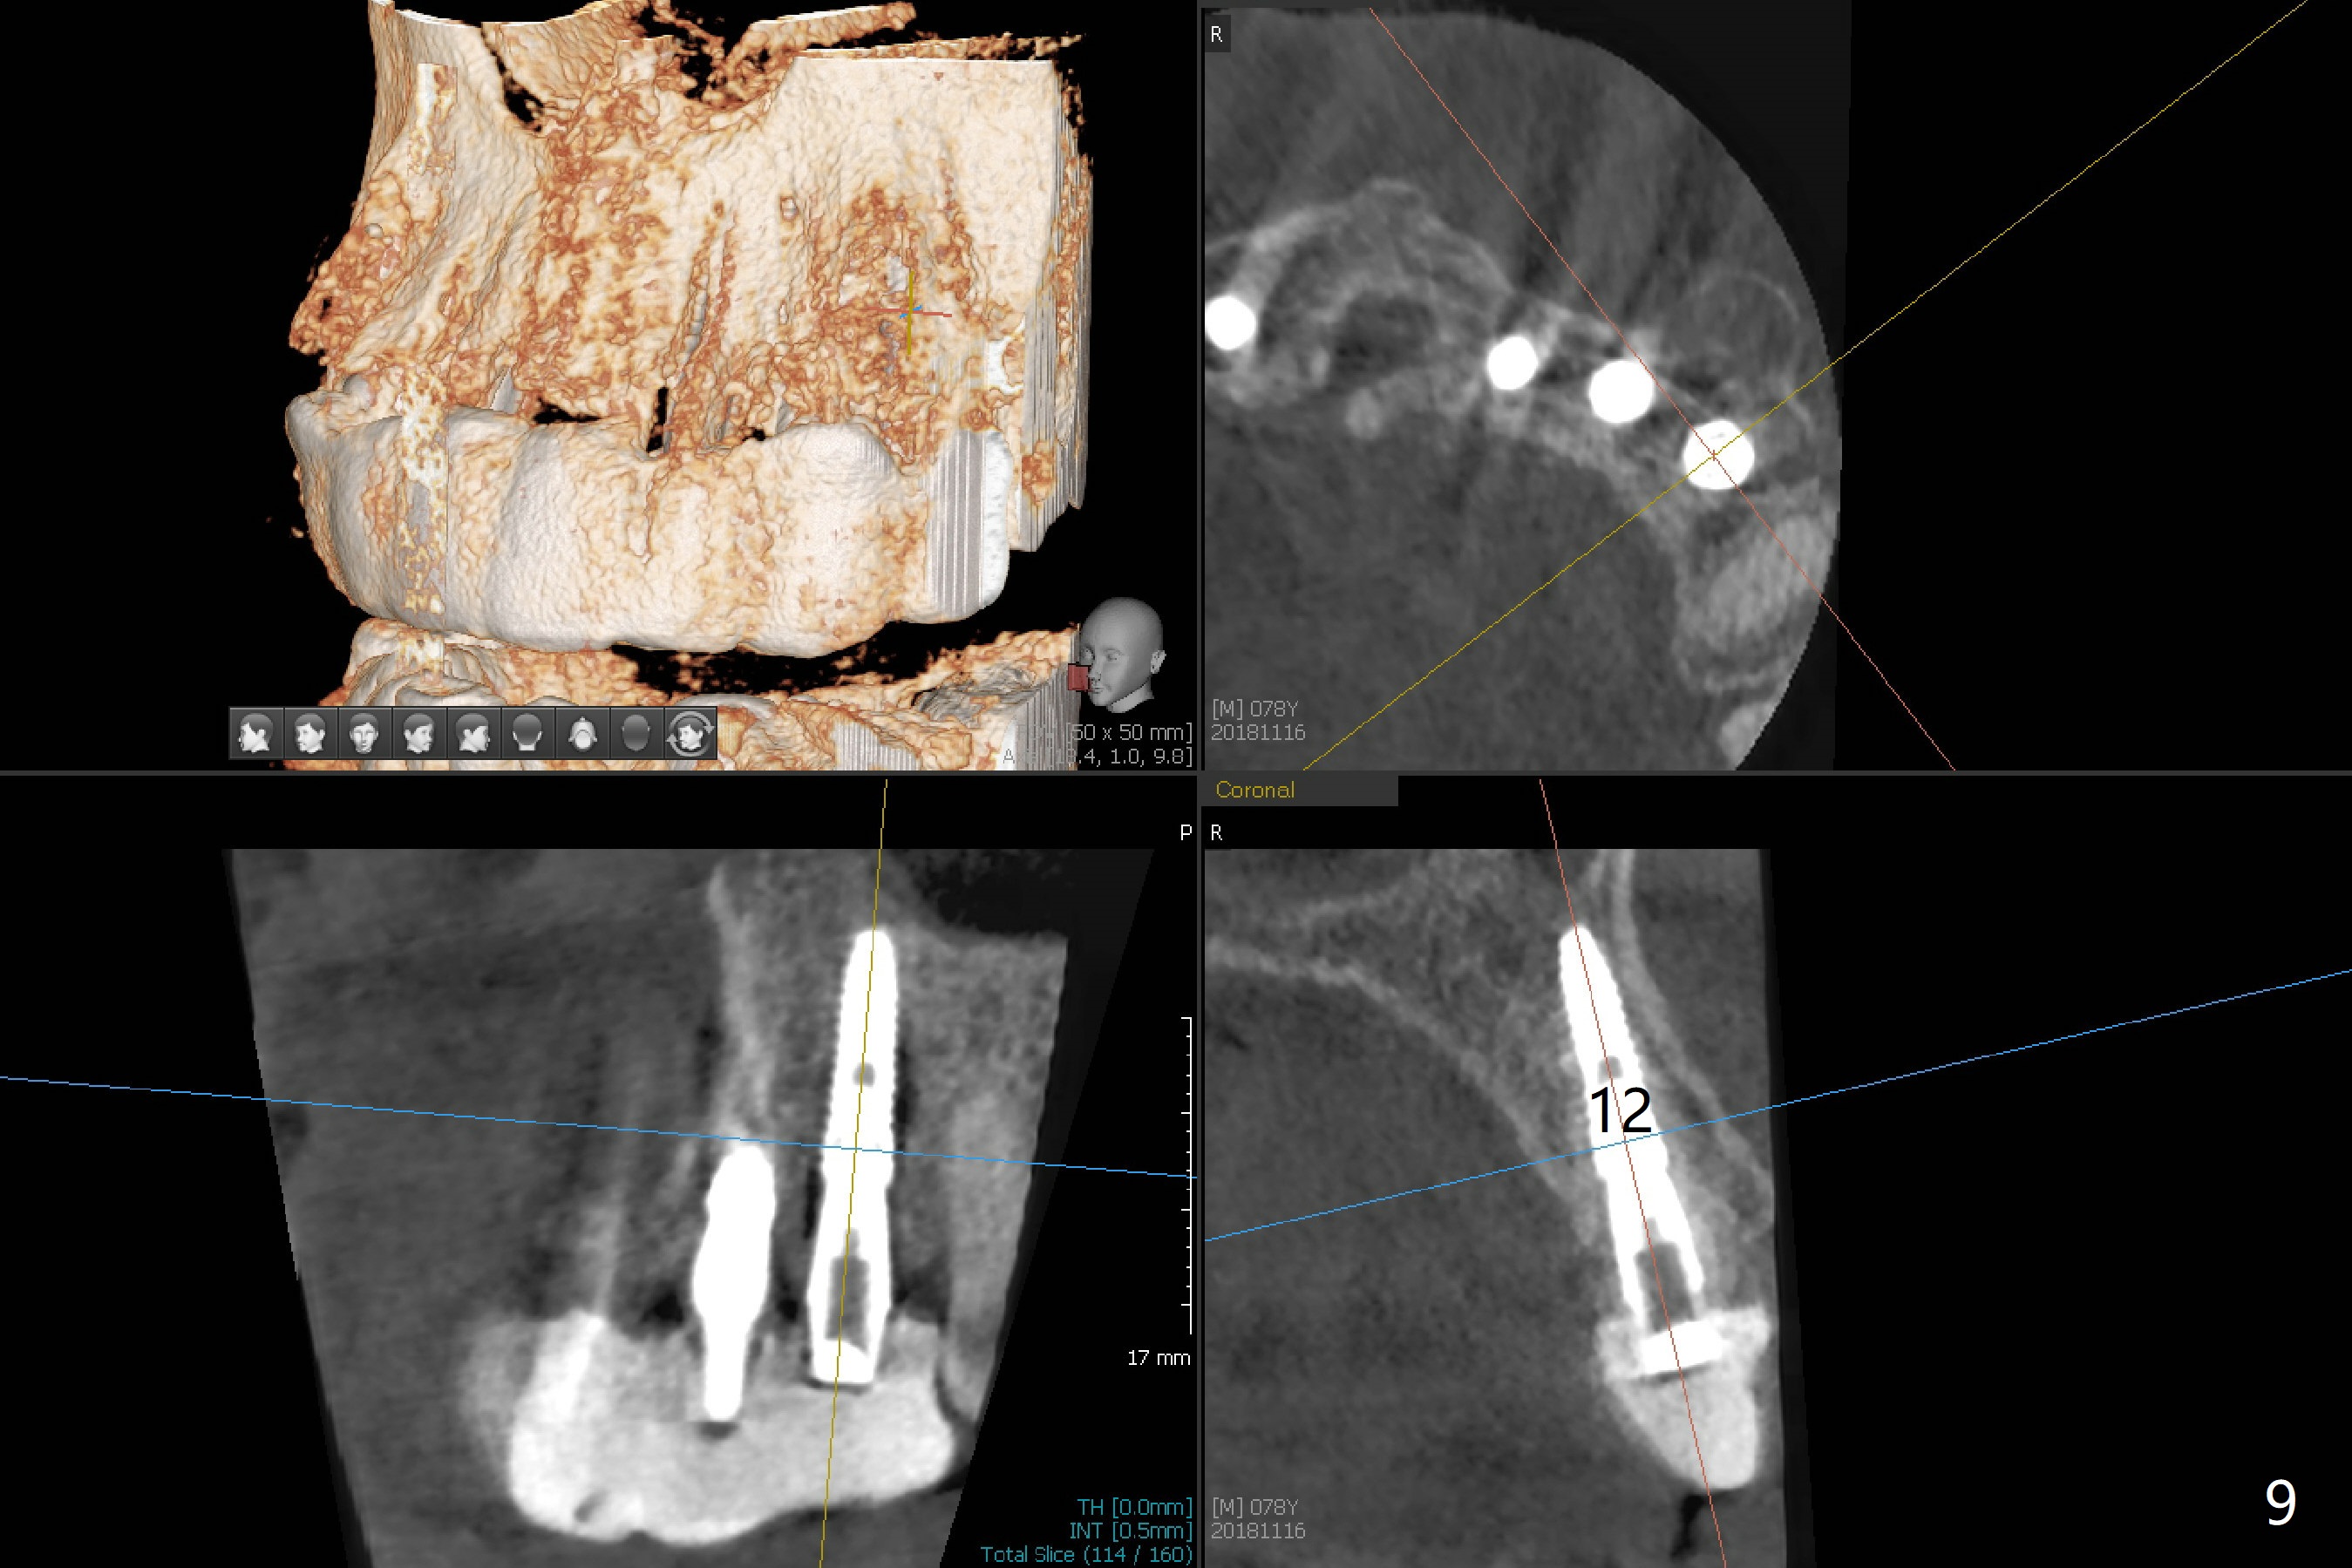

It is smooth and quick to finish osteotomy with guide at #6,7,10-12, but when 3 mm 1-piece implants are placed free hand at #7 and 10 (Fig.1,2), the gingival parts of the abutments contact the incisal edges of the lower incisors (anterior deep bite) in spite of effort to change the trajectory by repeated back and forth placement after use of Lindamann bur buccally. Following an immediate provisional (Fig.3,4), the occlusal surface of the posterior teeth are raised to eliminate anterior restoration interference. Immediate postop CBCT shows that the implants at #7 and 10 could be placed more buccally (Fig.6,7, as compared to the normal position at #6,11,12 (Fig.5,8,9)). Fig.10 was taken 2 days preop, while Fig.11-13 postop. Can we change 1-piece implants (3mm) at #7 and 10 to 2-piece one (3.5) and use angled or cementation abutments for easy restoration (Fig.14-16)?